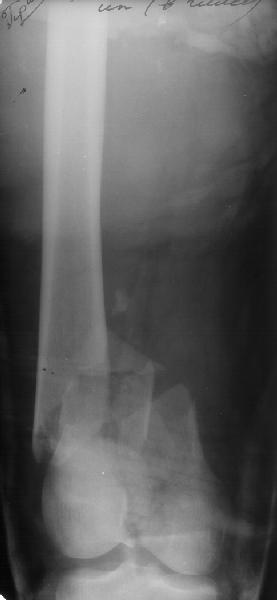

A mail 27 y.o. was operated Apr 2, 2002 2 weeks after injury (impact by a heavy construction) - he had open Gustilo II distal femoral fracture (image 1). Antegrade closed nailing by UFN 11 mm was performed (image 2). The second leg was amputated above the knee at the initial hosptial. To provide early weight bearing 6 mm locking screws were used so sll static holes were drilled accordingly. 2 months after the surgery he started to load the limb, before only knee ROM excersises were perfomed. The cyclic loadings produces stress riser and the nail was broken 10 days ago (image 3). Now he admitted to us again. It is the first case of such complication we meet. Now i plan to push the broken fragment distally and then perfrom retrograde nailing by UFN (distal femoral nails are not available in my settings). If the attempt would be too complicated we'll change to XF. Or plating is a good option here?